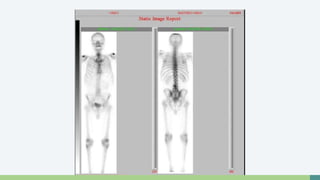

Gammagrafía Ósea

• Útil para detección de Metástasis Oseas

• Indicada en Pacientes con

• PSA +10

• Gleason +7

• Dolor Óseo

• Tecnecio 99

Gammagrafía Ósea •Útil para detección de Metástasis Oseas • Indicada en Pacientes con • PSA +10 • Gleason +7 • Dolor Óseo • Tecnecio 99